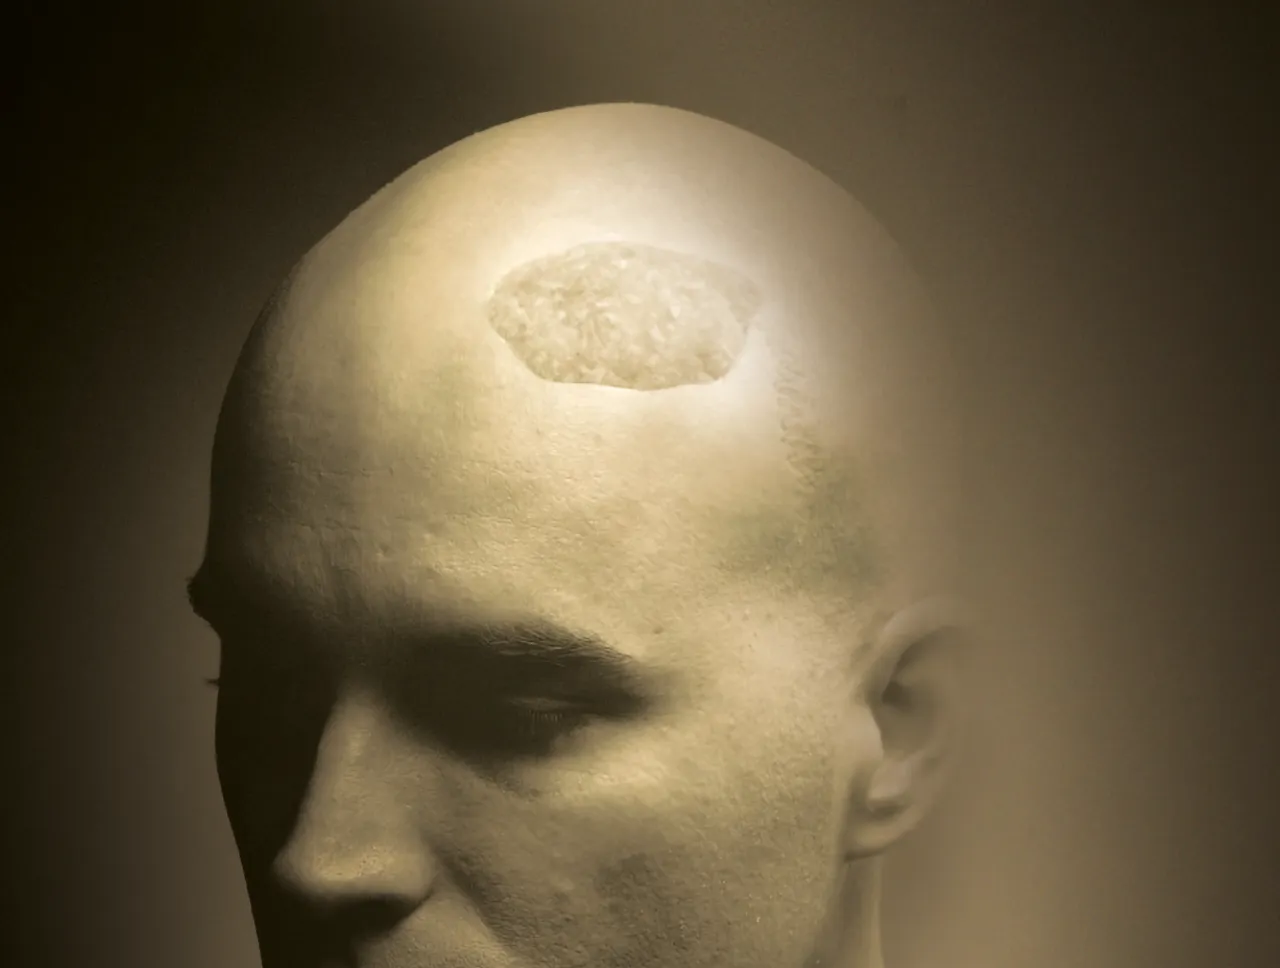

Craneoplastía

Implantes personalizados

El compromiso comienza con los casos más complejos para reconstrucción craneal por...

Matriz Ósea

Allogenix™ es un injerto de tejido moldeable listo para usar que combina DBM con un...